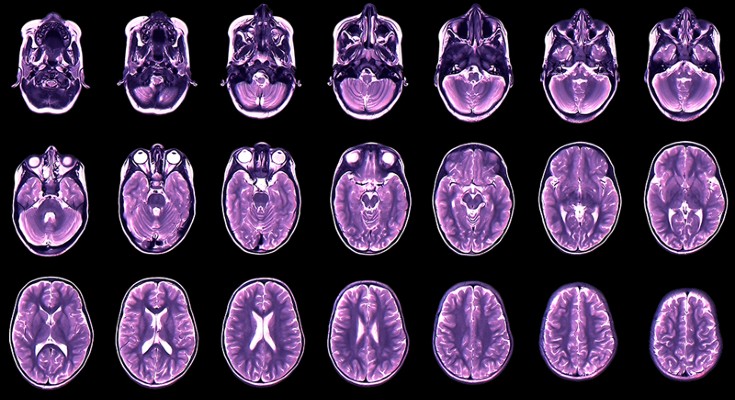

RNA-sequencing analysis of cells in the human cortex enabled identification of diverse cell types, revealing well-conserved architecture and homologous cell types as well as extensive differences when compared with datasets covering the analogous region of the mouse brain.

Whether cell types in the brain have been conserved during evolution is not clear. A comparison of the molecular recipes that define brain cell types in humans and mice reveals similarities and differences between species.

• Matthew G. Keefe

•  & Tomasz J. Nowakowski

The brain

Sam Falconer

The human brain isn’t much to look at. In the hand, it is a jelly-like mass, easily deformed by touch. But its unassuming appearance belies complex inner workings, many of which are still a mystery to scientists.